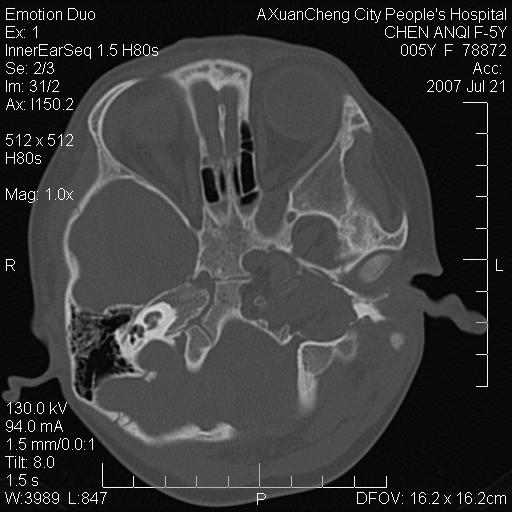

标题: PED0273:5岁,左耳流脓痛疼一周,颅底骨质破坏 [打印本页]

标题: PED0273:5岁,左耳流脓痛疼一周,颅底骨质破坏

患儿5岁,左耳流脓痛疼一周,左外耳道肉芽组织填塞 软组织窗显示病灶内结节状低密度影为气体密度

左侧中耳炎并胆脂瘤,左颞骨岩部骨质破坏并颅内感染积气。

考虑化脓性中耳乳突炎伴胆脂肪瘤形成并左颞叶感染,不除外合并嗜酸性肉芽肿.